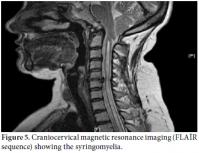

In the scintigraphic examination, we found increased activity involvement in both shoulders, especially in the right shoulder as well as on the right humeral head and in the distal phalanx of the finger. Both the scintigraphic and the radiological findings were compatible with secondary degenerative changes, especially in the benign bone pathologies (Figure 4). Furthermore, craniocervical magnetic resonance imaging (MRI) (especially FLAIR sequence) found cerebellar tonsillar herniation compatible with the Chiari type I malformation in the accompanying syrinx cavity in the cervical spinal cord (Figure 5). In addition, the arterial/venous Doppler ultrasonography (USG) results for both the lower and upper extremities were normal.